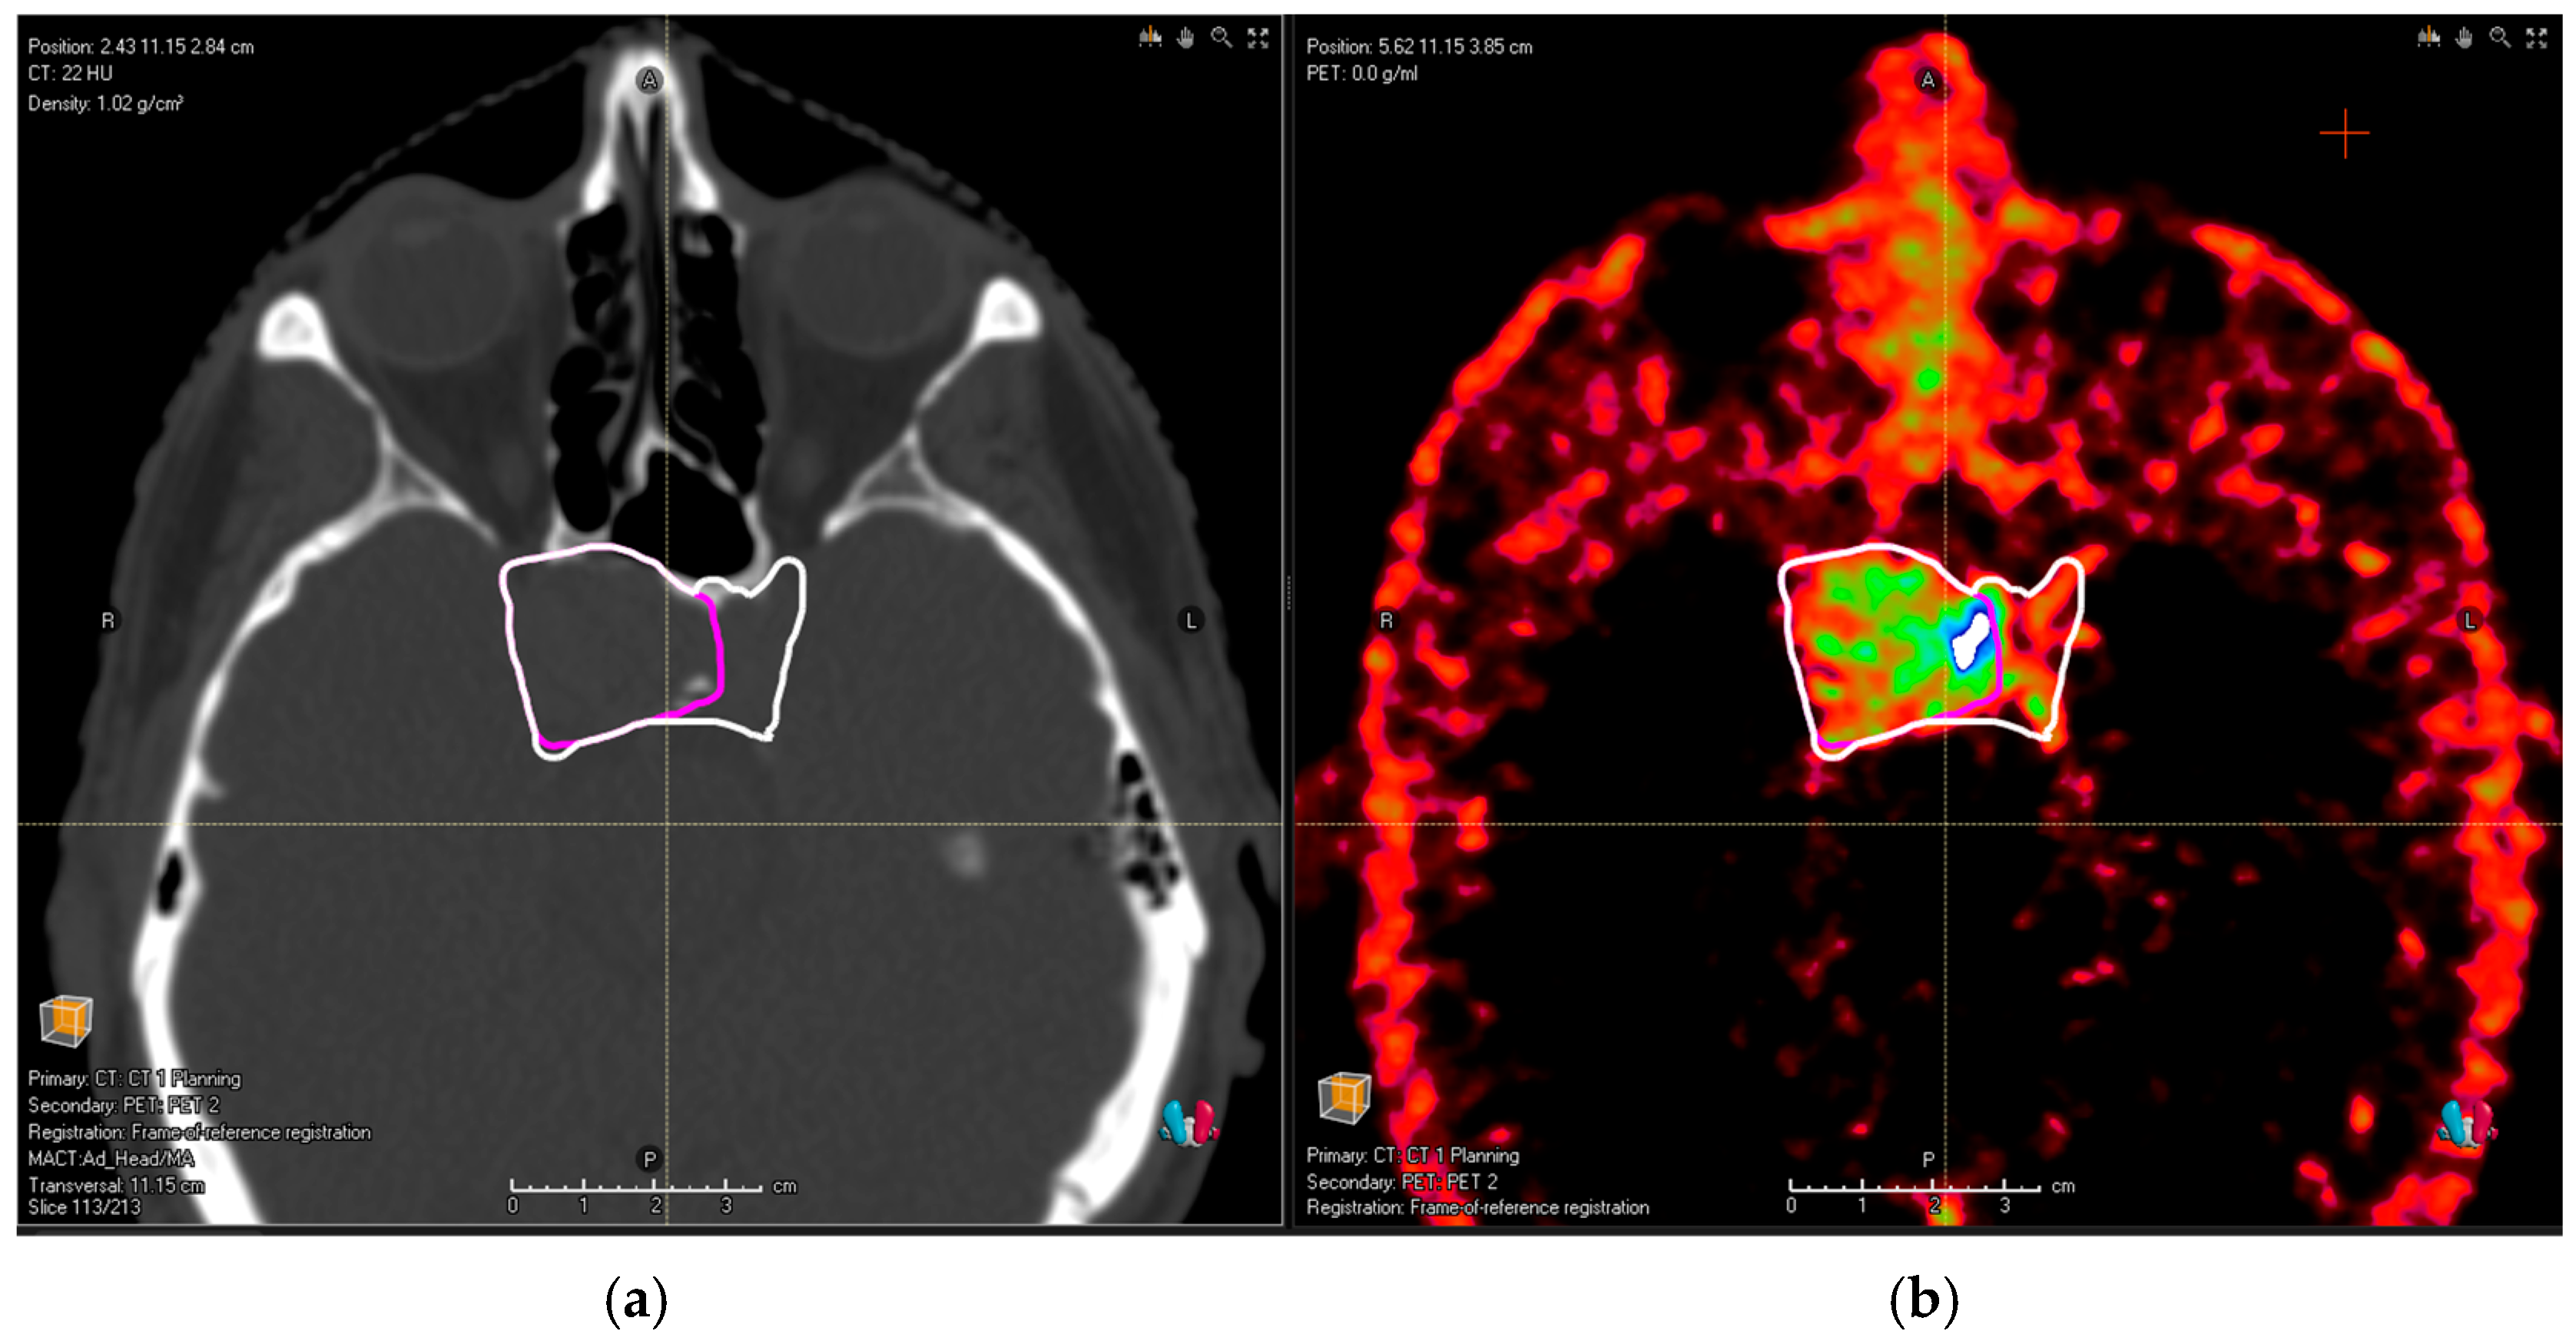

- PitNET with the bilateral involvement of cavernous sinus (as depicted in Figure 1);

Figure 1. (a) Planning the CT image of a patient with pituitary adenoma. Pink contour shows common MRI volume; after the addition of PET/CT, (b) the observers identified an infiltration in the left cavernous sinus (white contour). - Extensive bone infiltration in the frontobasis area from a case of an aggressive PitNET (as depicted in Figure 2).

In all these cases, the new tumor volume first identified with the aid of DOTA PET/CT should be considered relevant for the proton treatment plan. There was no relevant tumor volume missed by observers in MRI compared to PET/CT for glomus tumors. Figure 1a shows the planning CT image of a patient with pituitary adenoma; Figure 2a shows the planning CT image of a patient with an aggressive pituitary adenoma.